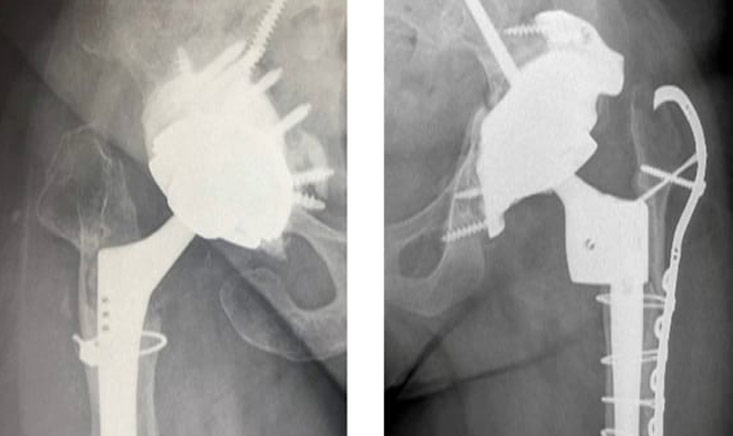

Used for 40 years in France, dual mobility cups have taken on a major role in the management of unstable total hip arthroplasties and those at risk of instability. Our KOLs compare the French vision with international practice.